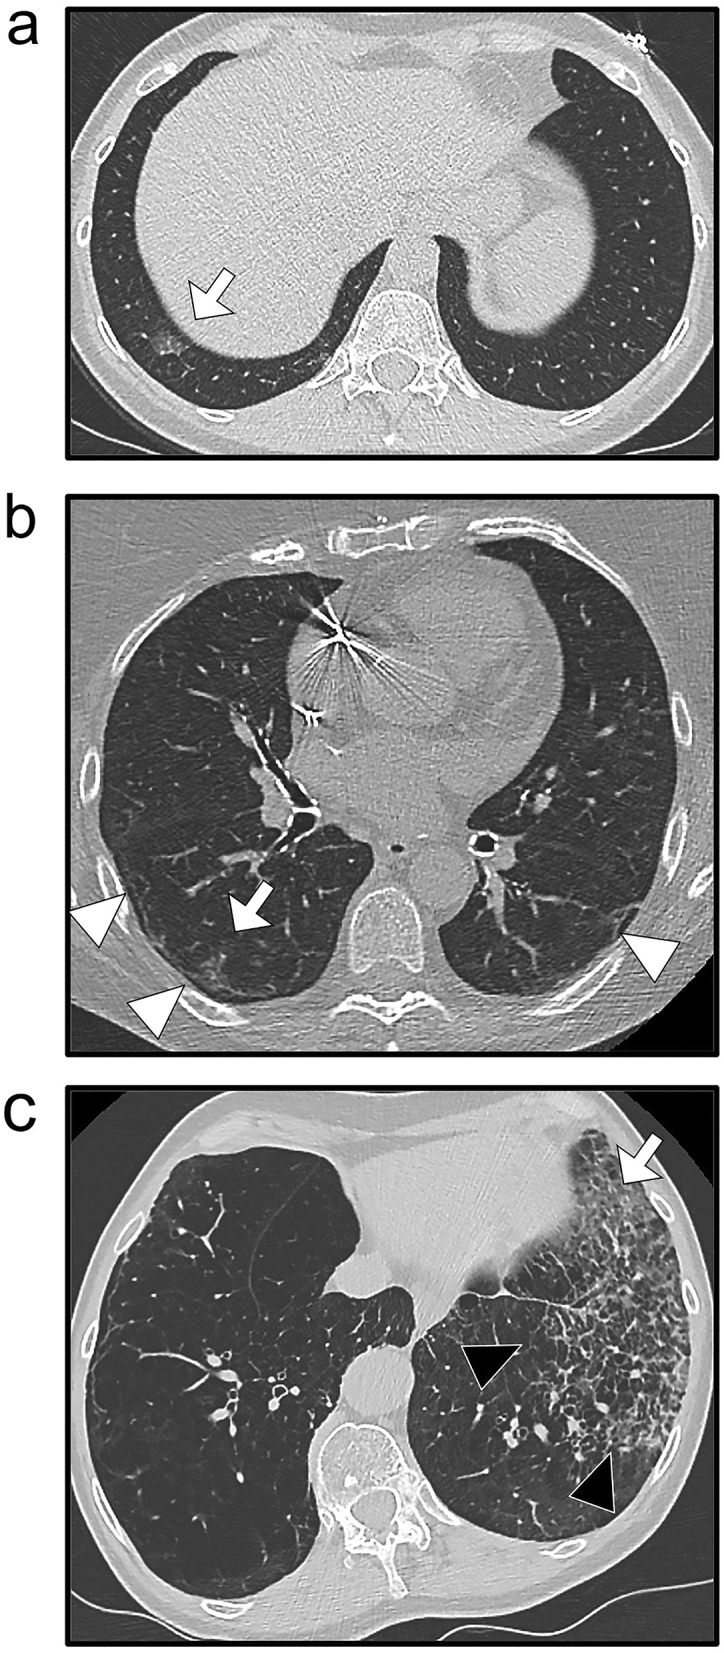

In the subgroup of patients with an indeterminate conclusion (4), the probabilities for RT-PCR + with the clinical-radiological Step-LR model were significantly higher for patients with RT-PCR + than for patients with RT-PCR− (0.63 ± 0.28 versus 0.39 ± 0.27, respectively, p = 0.004). Figure 5 illustrates the potential application of this model for patients with an indeterminate/compatible conclusion. An excel macro is provided in Supplementary Data 4 so that the interested reader can test the Step-LR models.

Added value of the final clinical-radiological model for patients with indeterminate/compatible radiological conclusions. (a) A 50-year-old woman presented at the emergency with chest pain, fever, and cough for less than one week. Chest CT showed a basal-predominant peripheral ground-glass opacity (GGO—white arrow) in the lower right lobe. The probability for RT-PCR + was 68.9%. (b) A 71-year-old woman presented at the emergency with cough, dyspnoea, fever and asthenia for 1–2 weeks. Chest CT showed bilateral peripheral fibrotic bands (white arrowheads) with a peripheral right GGO (white arrow). The probability for RT-PCR + was 65%. (c) A 61-year-old woman with a medical history of active smoking, emphysema and chronic obstructive pulmonary disease presented at the emergency with a cough, dyspnoea, fever and asthenia. Chest CT showed peripheral predominant intralobular reticulations in the lower left lobe (black arrowheads) with a single area of non-rounded GGO (white arrow). The probability for RT-PCR + was 57.9%. In the three cases, the RT-PCR was indeed positive.